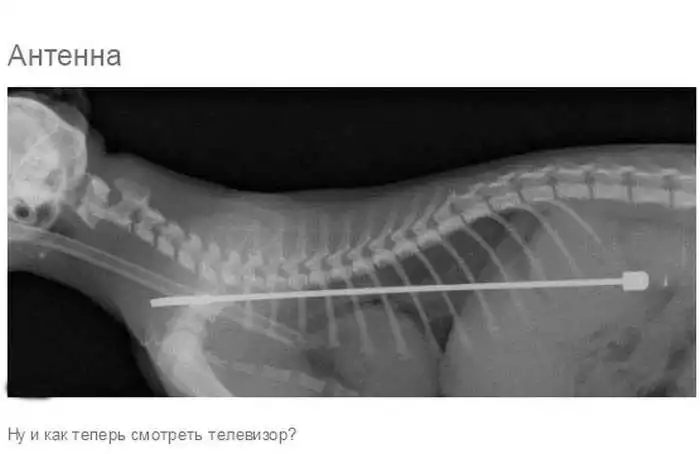

Что может оказаться в желудке собаки

Думаю, всем собачникам известно, что порой у собак бывают такие заскоки, когда они в прямом смысле слова жрут все подряд.